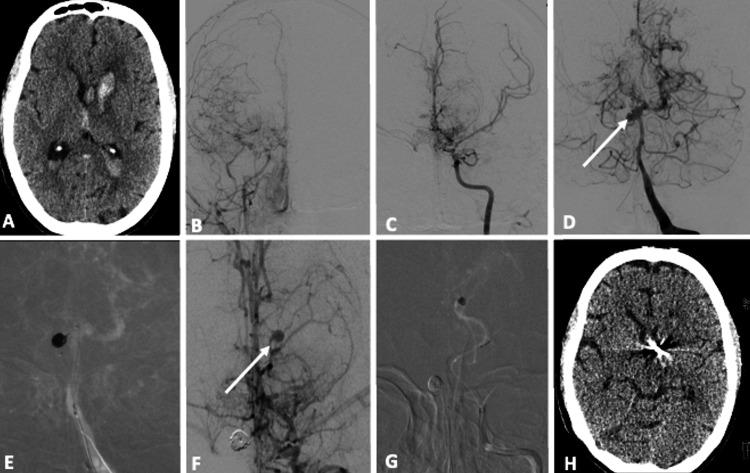

Background Moyamoya disease (MMD) can be a major cause of hemorrhagic stroke. Though extensive angiographic studies have been undertaken, the understanding of the association between aneurysms and MMD remains unanswered. In this study, we explore the association of the aneurysm with MMD and its management. We have also reviewed such associations described in the literature and how the present cases differ from those previously described. Materials and methods The clinical and radiologic data of moyamoya disease cases were accessed from medical and radiological records between January 2010 and July 2017. Two neuroradiologists independently analyzed the data and imaging details. Results Out of 103 patients with MMD, eight patients (7.77%) had associated intracranial aneurysms with eleven aneurysms. Out of the 11 aneurysms, five were the tip of the basilar artery aneurysms and were the most common location for aneurysm (45.5%), followed by lenticulostriate artery, PCA perforator, and distal ACA (DACA) in the P1 PCA, P2 PCA, and P3 PCA artery aneurysms. Out of eight patients, five (62.5%) had a hemorrhage on a non-contrast computed tomography (NCCT) scan of the brain, whereas three (37.5%) had an ischemic presentation. Out of 11 aneurysms, seven aneurysms, including three basilar tip aneurysms (unruptured) and one PCA perforator (ruptured), and three saccular PCA (P1, P2, and P3) (ruptured) were treated by endovascular coiling. Follow-up angiography showed stable aneurysmal occlusion except in one basilar tip, where recurrence was observed. Conclusions MMD-intracranial aneurysm is commonly observed in patients with intracranial hemorrhage and carries a higher risk of rupture. Therefore, identification of the aneurysm is essential for management. Endovascular treatment, either with coil or glue embolization, can be a safe and effective treatment method for such aneurysms with long-term good results.

在103例烟雾病患者中,8例(7.77%)伴有颅内动脉瘤,共11个动脉瘤。在这11个动脉瘤中,5个是基底动脉尖部动脉瘤,是动脉瘤最常见的部位(45.5%),其次是豆纹动脉、大脑后动脉穿支以及大脑前动脉远段(DACA)在大脑后动脉P1段、P2段和P3段的动脉瘤。在8例患者中,5例(62.5%)在脑部非增强计算机断层扫描(NCCT)上有出血表现,而3例(37.5%)有缺血表现。在11个动脉瘤中,7个动脉瘤,包括3个基底动脉尖部动脉瘤(未破裂)和1个大脑后动脉穿支动脉瘤(破裂),以及3个囊状大脑后动脉(P1、P2和P3)动脉瘤(破裂)通过血管内栓塞治疗。随访血管造影显示,除1个基底动脉尖部动脉瘤复发外,其余动脉瘤闭塞稳定。